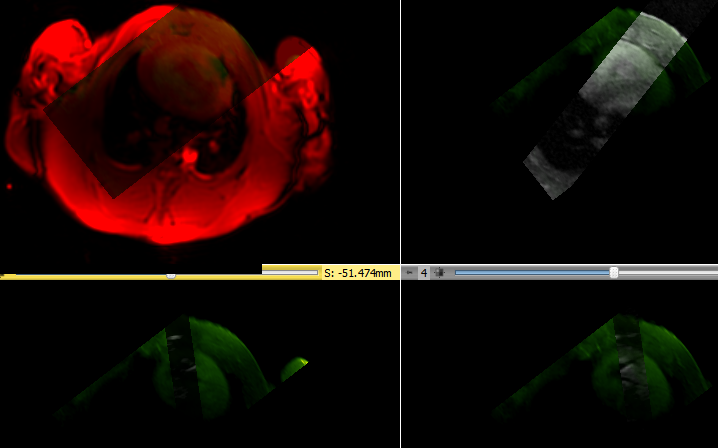

- The Post MN (manganese) MRI images of the stem cell area are transformed into the frame of reference of the current stem cell area image.(Top left) The Post MN (manganese) image of the stem cells (green) is oriented inside the fixed locator (red). (Top right) Previous 1 Post MN slice transformed (Bottom left) Previous 2 post MN image (Bottom right) Previous 2 post MN image.

- Place an ROI around the potential stem cells on the current Post MN image and found intensity 67.64+/-5.932